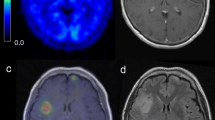

Type A, shown by astrocytic tumors, was a MET-TAC with a MET-SUV with a low or middle level in the initial phase, a rapid increase in the early phase, and a consistent or limited/slow increase in the late phase. The MET-SUV was markedly higher in the initial phase and had a tendency to increase more in early and late phases in GBM compared to AA and DA (Fig. 2a). MET-SUVs were significantly higher in early and late phases in GBM compared to AA, DA and the normal frontal cortex (*P < 0.05) (Fig. 2a). There was no significant difference in MET-SUVs between AA and DA (Fig. 2a). The MET-TAC of the normal frontal cortex belonged to this type, and the MET-SUVs of the normal frontal cortex were significantly lower than those of GBM, AA and DA (**P < 0.05) (Fig. 2a).

MET-TACs in brain tumors, the normal frontal cortex, confluence, and internal jugular vein. MET-SUVs were significantly higher in early and late phases (*P < 0.05) and showed a more marked increasing tendency in the early phase in GBM compared to AA, DA and normal frontal cortex (a). There was no significant difference in MET-SUVs between AA and DA (a). The MET-SUVs of the normal frontal cortex were significantly lower than those of GBM, AA and DA (**P < 0.05) (a). MET-SUVs were higher in the initial phase and showed a tendency to increase more in the early phase in AO compared to AOA, OD, and OA (b). There was no significant difference in MET-SUVs among AO, AOA, OD and OA (b). A tendency to decrease more was seen in the late phase in AOA, OD, and OA compared to AO (b). The MET-SUVs of OA were markedly lower than those of AOA and OD (b). MET-SUV with a low level in the initial phase, a rapid increase in the early phase, and a continuous increase in the late phase in PCNSL (c). MET-SUV with a high level in the initial phase, a rapid decrease in the early phase, and a continuous decrease in the late phase in meningiomas, hemagioblastomas, the confluence, and internal jugular vein (d). Error bars represent ± SEM, the 95% confidence interval. MET-TAC time-activity curve of maximum tumor MET-standardized uptake value, MET-SUV maximum tumor MET-standardized uptake value, DA diffuse astrocytoma, OD oligodendroglioma, OA oligoastrocytoma, AA anaplastic astrocytoma, AO anaplastic oligodendroglioma, AOA anaplastic oligoastrocytoma, GBM glioblastoma multiforme, PCNSL primary central nervous system lymphoma

Type O, shown by tumors that included an oligodendroglial component, was a MET-TAC with a MET-SUV with a low or middle level in the initial phase, a rapid increase in the early phase, and a limited/slow decrease in the late phase. The MET-SUV was higher in the initial phase and had a tendency to increase more in the early phase in AO compared to AOA, OD, and OA (Fig. 2b). There was no significant difference in MET-SUVs among AO, AOA, OD and OA (Fig. 2b). A tendency to decrease more was seen in the late phase in AOA, OD, and OA compared to AO (Fig. 2b). The MET-SUVs of OA were markedly lower than those of AOA and OD (Fig. 2b).

Type L, shown by PCNSL, was a MET-TAC with a MET-SUV with a low level in the initial phase, a rapid increase in the early phase, and a continuous increase in the late phase (Fig. 2c).

Type M/H, shown by meningiomas and hemagioblastomas, was a MET-TAC with a MET-SUV with a high level in the initial phase, a rapid decrease in the early phase, and a continuous decrease in the late phase (Fig. 2d). The MET-TACs of the confluence and internal jugular vein belonged to this type (Fig. 2d).

Several static MET-PET studies have reported a higher diagnostic accuracy compared to MRI, but still found limited accuracy due to high overlap between WHO grades [22]. Dynamic analysis of FET-PET uptake improved the differential diagnosis between WHO grade II and WHO grades III/IV gliomas. WHO grade II gliomas typically showed steadily increasing time-activity curves as compared to WHO grades III/IV gliomas, in which the early peak activity occurred around 10–20 min after injection, and was followed by a decrease of FET uptake [9]. However, even with dynamic analysis of MET-PET, the uptake characteristics did not allow for classification of low-grade versus high-grade gliomas [20]. In our study, although there were no significant differences in MET-SUVs among Type O, MET-SUVs were significantly higher in all phases in GBM compared to AA and DA (Fig. 2). When limited to astrocytic tumors, MET-TAC analysis may be useful for WHO grading.

GBM and PCNSL sometimes have similar features on conventional MRI. 18F-FDG PET may provide useful information for distinguishing WHO grade III/IV gliomas from other malignant brain tumors, but its specificity is limited. Importantly, the maximum SUV was significantly higher in PCNSL than in GBM [9]. In a dynamic MET-PET study, the ratio of the maximum SUV in late and early phases was considered to be a good diagnostic test when encountering difficulties in the differential diagnosis between GBM and PCNSL [24]. In our study, when we set the cutoff of the SLOPE in the late phase to 0.54 h−1 for the differentiation of GBM from PCNSL, the diagnostic accuracy was 100% sensitivity and 67.3% specificity. Our results were similar to the previous study, which suggests that dynamic MET-PET could be useful for the differential diagnosis between GBM and PCNSL.